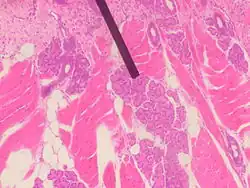

Von Ebner's gland

Human Von Ebner's gland

Von Ebner's glands, also called Ebner's glands or gustatory glands, are exocrine glands found in the mouth. More specifically, they are serous salivary glands which reside adjacent to the moats surrounding the circumvallate and foliate papillae just anterior to the posterior third of the tongue in its submucosa, anterior to the terminal sulcus.

Von Ebner's glands secrete lingual lipase,[1] beginning the process of lipid hydrolysis in the mouth. These glands empty their serous secretion into the base of the moats around the foliate and circumvallate papillae. This secretion presumably flushes material from the mouth to enable the taste buds to respond rapidly to changing stimuli.